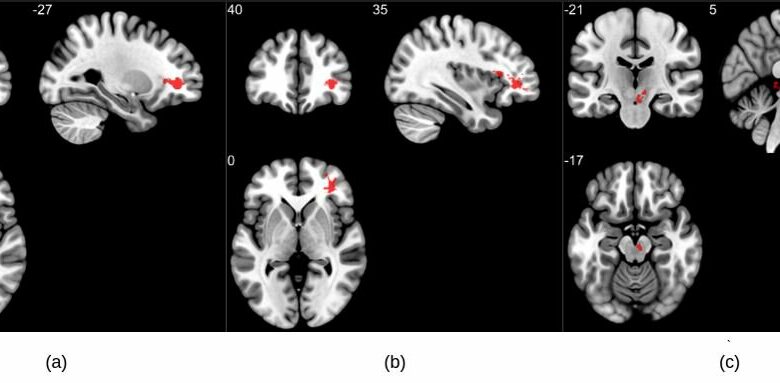

Análise de grupo em imagens ponderadas por suscetibilidade exibindo valores de imagens ponderadas por suscetibilidade mais altos no grupo COVID quando comparado a controles saudáveis. Três grupos significativos foram encontrados principalmente nas regiões de substância branca do córtex pré-frontal e no tronco cerebral. Os aglomerados (a) e (b) são observados bilateralmente na substância branca cerebral perto do giro orbitofrontal, enquanto (c) está localizado na região do mesencéfalo. Crédito: RSNA e Sapna S. Mishra

Os resultados da ressonância magnética mostraram que os pacientes que se recuperaram do COVID-19 apresentaram valores de suscetibilidade significativamente mais altos no lobo frontal e no tronco cerebral em comparação com controles saudáveis. Os aglomerados obtidos no lobo frontal mostram principalmente diferenças na substância branca.

Porções do giro frontal orbital inferior esquerdo (uma região chave para a compreensão e produção da linguagem) e giro frontal orbital inferior direito (associado a várias funções cognitivas, incluindo atenção, inibição motora e imaginação, bem como processos cognitivos sociais) e os adjacentes substância branca áreas compunham o lóbulo frontal clusters.

Os pesquisadores também encontraram uma diferença significativa na região do diencéfalo ventral direito do tronco cerebral. Esta região está associada a muitas funções corporais cruciais, incluindo a coordenação com o sistema endócrino para liberar hormônios, retransmitir sinais sensoriais e motores para o córtex cerebral e regulando ritmos circadianos (o ciclo sono-vigília).